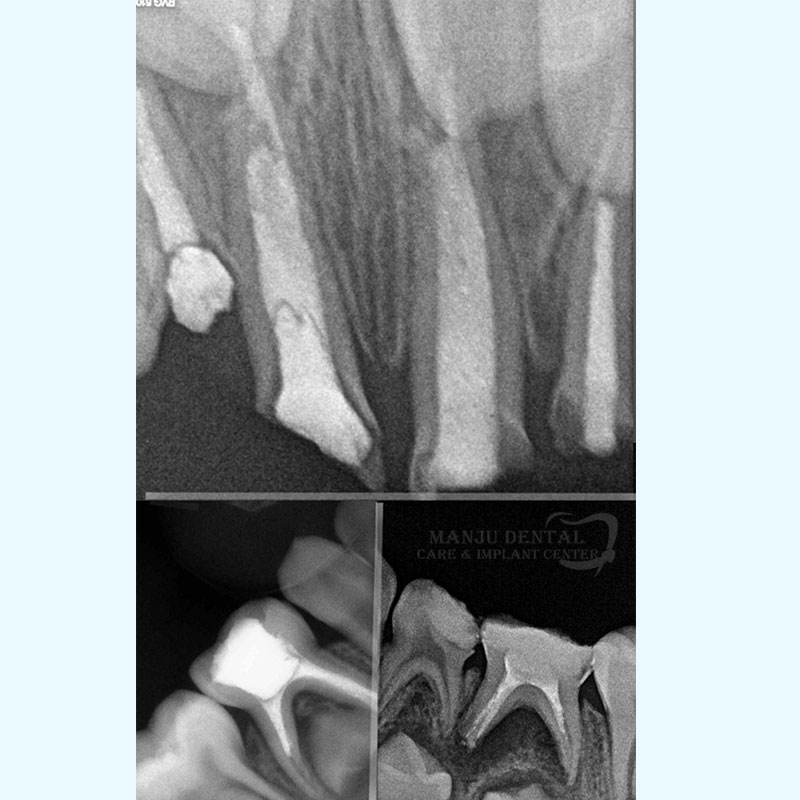

• Interpret x-rays and other diagnostic tests

Pulpectomy of Primary Teeth Keeping It Strong Till Its Time To Go